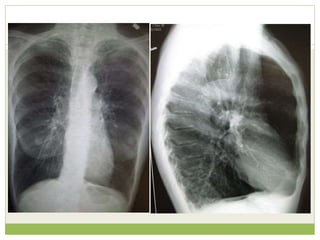

๏‚— Pulmonary edema is fluid accumulation in the air

spaces and parenchyma of the lungs. It leads to

impaired gas exchange and may cause respiratory

failure.

๏‚— It is due to either failure of the left ventricle of the

heart to adequately remove blood from the

pulmonary circulation ("cardiogenic pulmonary

edema"), or an injury to the lung parenchyma or

vasculature of the lung ("noncardiogenic pulmonary

edema")

๏‚— The key findings of cardiogenic pulmonary edema

Kerley B lines (septal lines)

๏‚ก Seen at the lung bases, usually no more than 1 mm thick and 1 cm

long, perpendicular to the pleural surface

๏‚— Pleural effusions

๏‚ก Usually bilateral, frequently the right side being larger than the left

๏‚ก If unilateral, more often on the right

๏‚— Fluid in the fissures

๏‚ก Thickening of the major or minor fissure

๏‚— Peribronchial cuffing

๏‚ก Visualization of small doughnut-shaped rings representing fluid in

thickened bronchial walls

๏‚— Non-cardiogenic pulmonary edema

๏‚ก Bilateral, peripheral air space disease with air bronchograms

or central bat-wing pattern

๏‚ก Kerley B lines and pleural effusions are uncommon

๏‚ก Typically occurs 48 hours or more after the initial insult

๏‚ก Stabilizes at around five days and may take weeks to

completely clear

๏‚ก On CT

๏ƒท Gravity-dependent consolidation or ground glass opacification

๏ƒท Air bronchograms are common